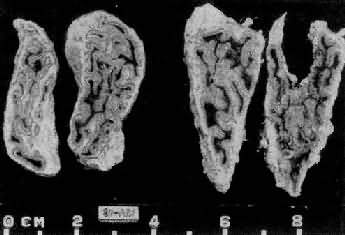

1.垂体性Cushing综合征 主要由垂体ACTH细胞腺瘤所引起,少数由于下丘脑异常分泌过多的促皮质释放因子(CRF)所致。血清中ACTH增高,双侧肾上腺呈弥漫性中度肥大,重量可达20g(正常8g左右),切面皮质厚度可超过2mm,呈脑回状。镜下主要是网状带及束状带细胞增生(图15-13、图15-14)。

图15-13 肾上腺皮质弥漫增生(大体)

肾上腺肥大,皮质弥漫性增厚,切面呈脑回状